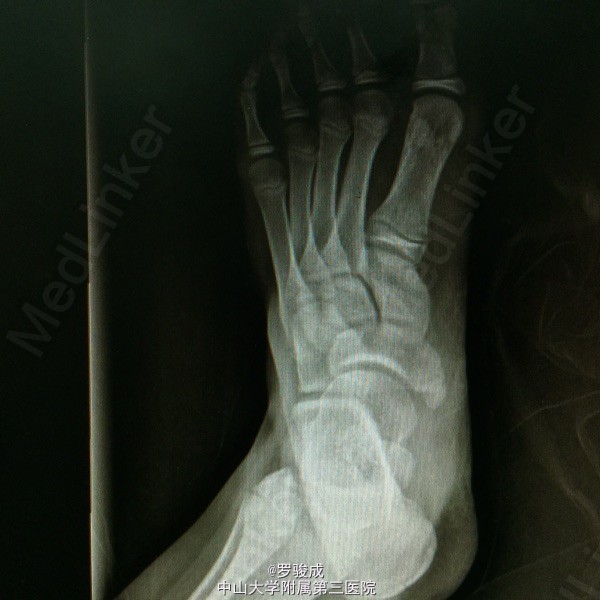

左足内侧疼痛2年余 两年余前运动后出现左足内侧疼痛,伴胀痛,无放射痛,无足部麻木。近来症状加重,遂前来我院就诊,X线提示左足副舟骨综合症。

左足内侧弓副舟骨表面硬性突起,无红肿,皮肤温度无升高,压痛明显。左足神经血运及感觉良好

诊断为左足副舟骨综合症。 行左足副舟骨清理融合术

足副舟骨综合症是一种先天性疾病,是舟骨结节部第二化骨中心的先天异常,在舟骨结节处形成一个独立的副骨。 足内侧隆起,久站或行走较长时, 感足底内侧疼痛。